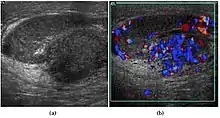

At ultrasound, the findings of acute epididymitis include an enlarged hypoechoic or hyperechoic (presumably secondary to hemorrhage) epididymis [Fig. 20a]. Other signs of inflammation such as increased vascularity, reactive hydrocele, pyocele and scrotal wall thickening may also be present. Testicular involvement is confirmed by the presence of testicular enlargement and an inhomogeneous echotexture. Hypervascularity on color Doppler images [Fig. 20b] is a well-established diagnostic criterion and may be the only imaging finding of epididymo-orchitis in some men.

Doppler ultrasound of epididymitis, seen as a substantial increase in blood flow in the left epididymis (top image), while it is normal in the right (bottom image). The thickness of the epididymis (between yellow crosses) is only slightly increased (7 mm).

Doppler ultrasound of the scrotum of the same case, in the axial plane, showing orchitis (as part of epididymo-orchitis) as hypoechogenic and slightly heterogenic left testicular tissue (right in image), with an increased blood flow. There is also swelling of peritesticular tissue.